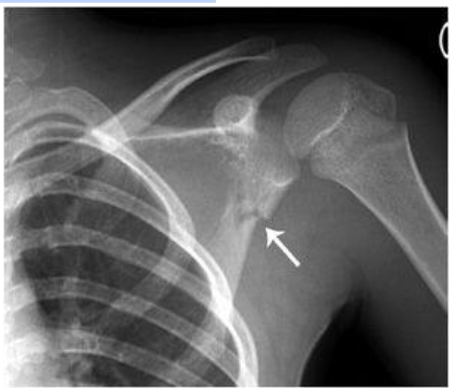

Metaphyseal Fractures

These are also known as bucket handle/corner fractures. These are the most SPECIFIC and PATHOGNOMONIC for nonaccidental trauma. This type of injury often occurs as microfractures from whiplash/shearing forces. This often presents exclusively in children under 2 years old because they are small enough to be shaken and not enough muscle development has occurred to protect their own limbs. However, please check patient’s birth history! In newborns, this can be a finding that can occur after traumatic deliveries where the baby presents in the breech position.